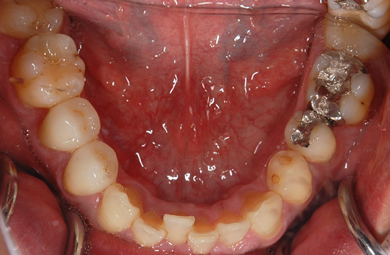

| 性別/年齢 | 男性 / 33歳 | ||||||||||||||||||||||||||||||||

| 治療方針 | 透明感のあるオールセラミックを使用して審美的・機能的回復を行う。 | ||||||||||||||||||||||||||||||||

| 治療内容 | オールセラミック6本(オールセラミック用の土台2本) | ||||||||||||||||||||||||||||||||

| 総治療費 | 741,129円 | ||||||||||||||||||||||||||||||||

| 治療期間 | 6ヶ月 |